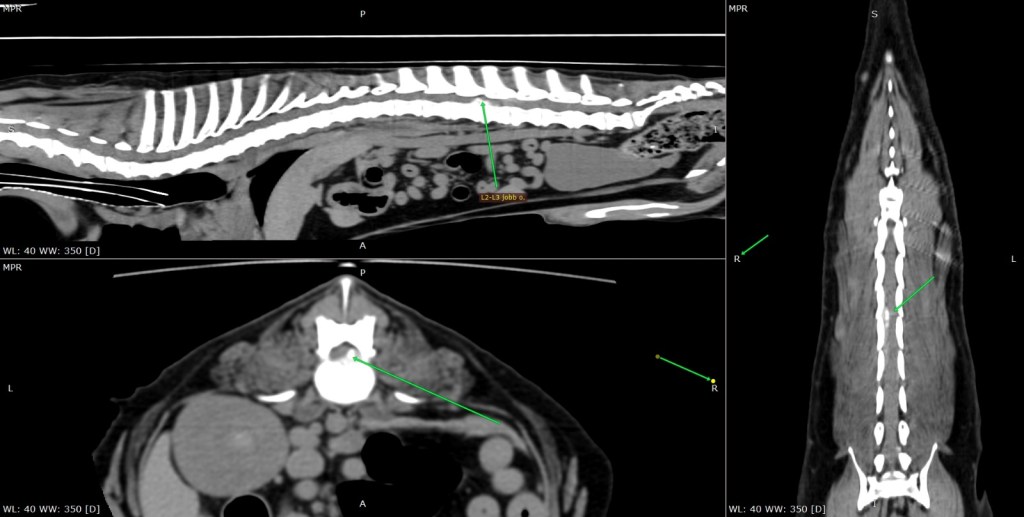

Gestern wurde unser Partnertierheim auf den Dackelrüden Tücsi aufmerksam. Dieser hat eine Familie, die ganz verzweifelt nach Hilfe für Tücsi suchte. Der Dackel Rüde hatte einen üblen Bandscheibenvorfall, wodurch er paralysiert war und nicht mehr laufen konnte. Tücsi hatte starke Schmerzen und eine OP war unabdingbar. Der Mann würde für Tücsi alles tun, nur fehlen ihm die finanziellen Mittel für den Eingriff und er wusste nicht, was er tun soll. Die OP war sofort erforderlich, also besprachen wir uns mit unseren Partnern und sicherten zu, in der Finanzierung zu helfen, damit Tücsi schmerzfrei weiterleben kann. Tücsi wurde also in die Tierklinik verbracht, ein CT erstellt und operiert. Die OP verlief erfolgreich und heute Morgen bekamen wir die Nachricht, dass der Rüde heute wieder nach Hause zu seiner Familie darf.